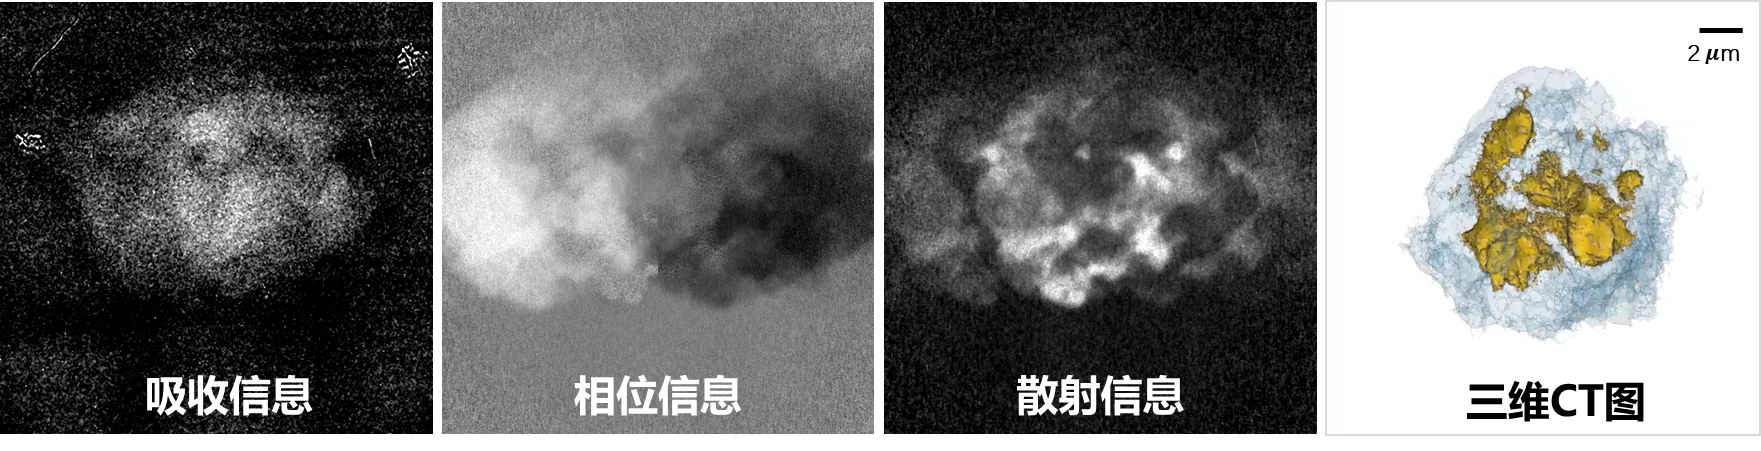

图4:利用本仪器获得的细胞样品的成像结果,从左到右依次为:吸收衬度、相位衬度、散射衬度、三维相位CT图。

经过充分质询与讨论,专家组一致认为:基于新型X射线波带片与光栅干涉仪相融合的成像原理,成功研制了国内首台实验室级多衬度(吸收、相位、散射)纳米CT成像科研仪器,Siemens星状卡测试结果表明仪器具备了28.5nm空间分辨的成像能力,核心X射线光学元件(波带片、光栅、分辨率卡等)均实现国产化。仪器工作状态良好,关键技术指标达到预期目标,部分技术指标达到国际先进水平,具备开展相关实验与应用研究的能力,同意通过现场测试。